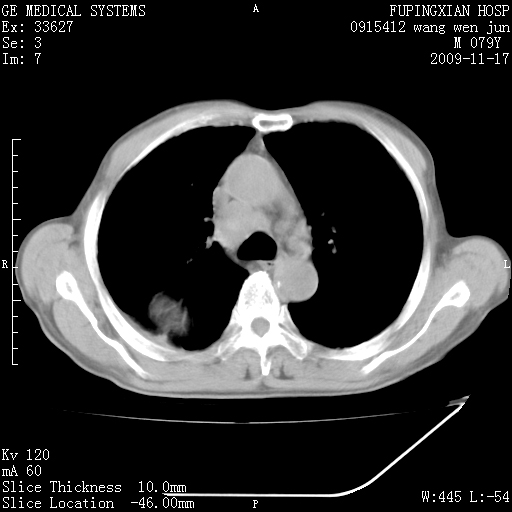

肿块ct值约15--30hu

肺外病变,考虑神经源性肿瘤可能性大

良性肺外病变,胸膜孤立性纤维瘤>胸膜良性间皮瘤>肋间神经来源神经鞘瘤。

建议 做个ct增强扫描,主肺动脉窗有可疑淋巴结。

纵膈内确实有淋巴结肿大,邻近肋骨骨质也不太均匀,考虑肺癌并转移

右侧肿块,最大径位于肺内,边界光滑锐利,密度均匀,局部胸膜增厚,纵隔内见明显肿大淋巴结。

右侧肺癌伴纵隔淋巴结转移不能出外。建议穿刺活检。鉴别诊断:1.神经源肿瘤,位置应该在脊柱旁。此例靠外。2.良性肿瘤:纵隔肿大淋巴结无法解释。3:胸膜肿瘤,最大径应该在胸壁,应该伴有胸水。

肿块与胸壁交界处胸膜被撑起,并见胸膜下脂肪层,考虑肺外病变。